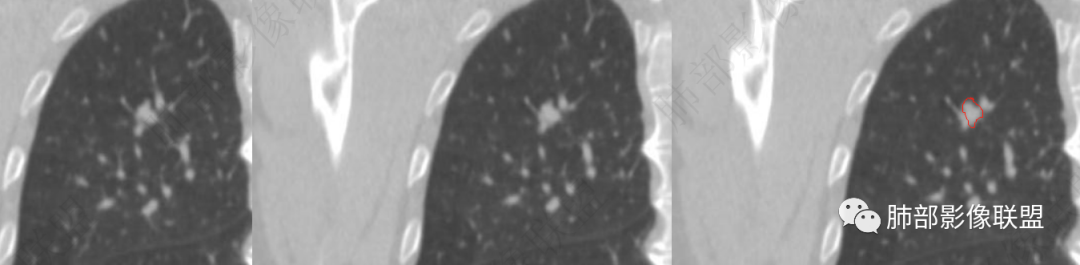

矢状位是这个吗

应该沿病灶长轴建

目前观察到的是:

密度均匀

边缘清楚、光滑,长轴方向较平直

缺点是没看清近端的支气管

4、矢状位示病灶沿肺动脉长轴走形,边缘较平直;